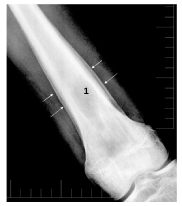

Fig. 118.2 Ostéomyélite chronique.

Radiographie de l’extrémité inférieure du fémur gauche de face avec une lacune centromédullaire bien limitée (1) et des appositions périostées continues épaisses en regard (flèches).

Source : CERF, CNEBMN, 2022.